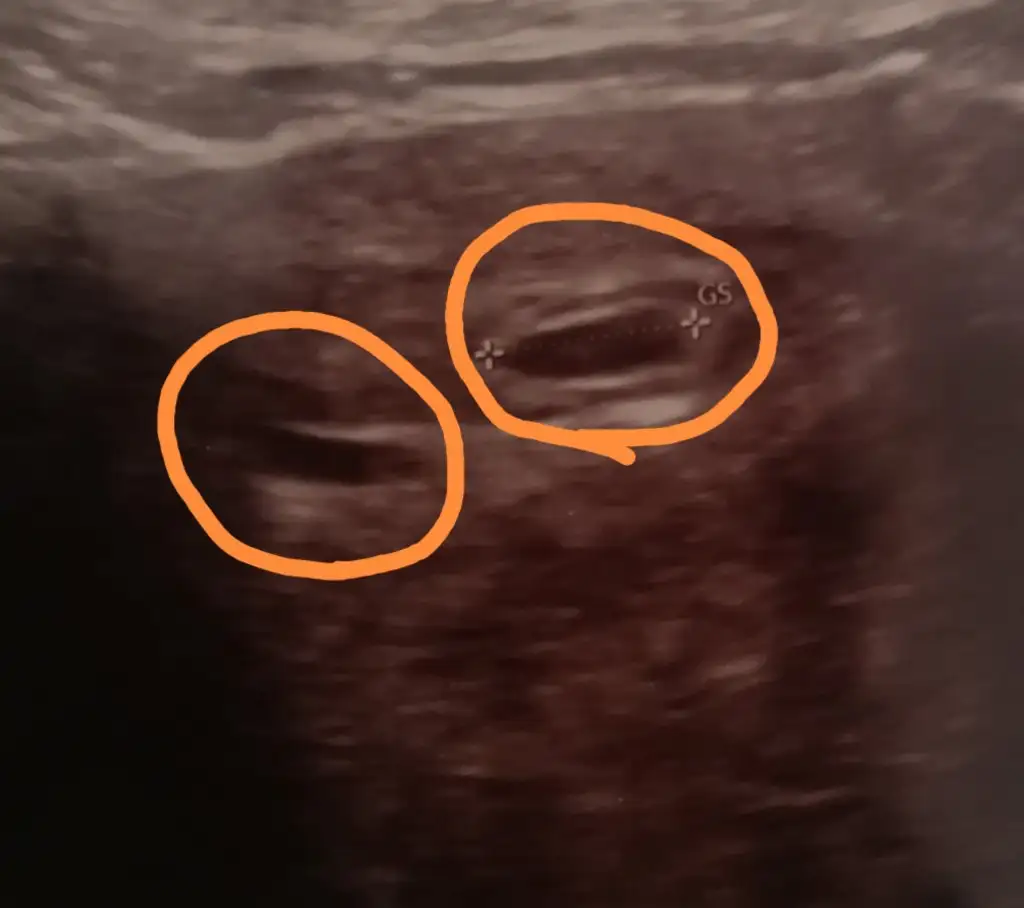

aslında kese gibi duruyor ama tabii çok iyi teknik donanıma sahip değilim. bazı durumlarda kesenin içi oluşmadan falan sağlıksızsa kese bozulup kaybolabiliyor. belki öyle bir durum olabilir. diğer doktor netleşmeden ümit vermek istememiş olabilir. benim de ilk ultrasonumda tek kese netti 2. de olabilir ama iyi göremiyorum sonraki kontrolde bakalım dedi doktorum. sonrakinde netleşmişti 2. kese. sizin de bir sonrakinde netleşir. hayırla sağlıkla gelsin/lerMerhaba, benim 5 yaşında bir kızım var ve tekrar hamile olduğumu öğrendim. Ama bir doktor iki tane kese var dedi yani ikiz dedi. Başka bir doktora gittim o da 2.nin kese olduğunu düşünmüyorum dedi.

Fotoya bakar mısınız acaba sizce ikiz mi? Doktor 1 hafta sonra gel kalp atıslarına bakalm dedi. Diğeri kese değilse ne olabilir acaba?

Bana da iki kese gibi geldi. Ben de 6 haftalıkken gittiğimde görülmüştü iki kese de ondan önce anlamamıştı doktor. Hayırlısı olsun ikiz çok güzel bence şanslı hissedin tüm olumsuzlukları kafanızdan çıkartınMerhaba, benim 5 yaşında bir kızım var ve tekrar hamile olduğumu öğrendim. Ama bir doktor iki tane kese var dedi yani ikiz dedi. Başka bir doktora gittim o da 2.nin kese olduğunu düşünmüyorum dedi.